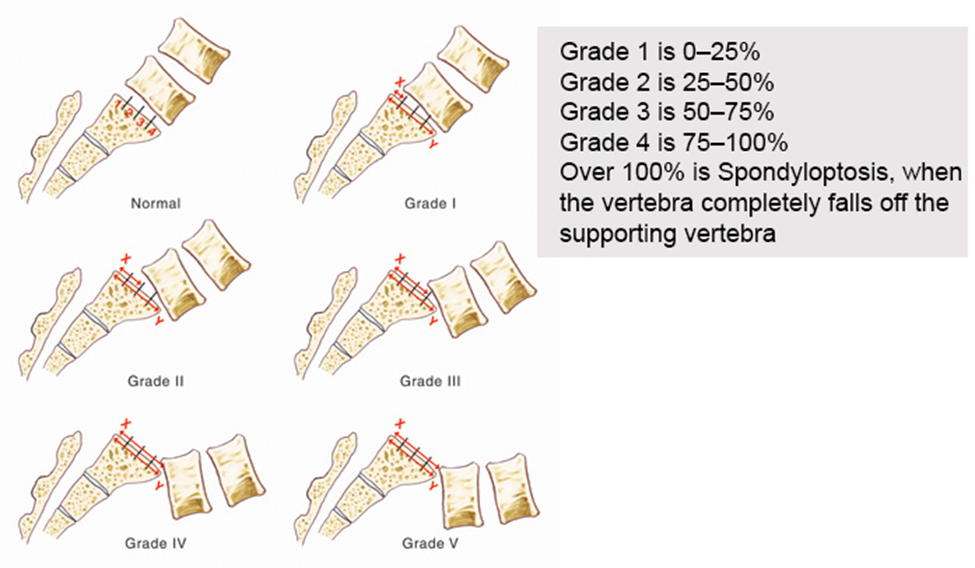

Là sư trượt ra trước của một thân đốt sống so với đốt sống khác, hay gặp nhất là đốt sống trên nằm ra trước so đốt sống bên dưới. Vị trí thường gặp là L5S1, kế đến là L4L5. Bảng 1 phân loại mức độ trượt theo Meyerding (hình 3).

Bảng 1: Phân độ trượt cột sống

| Độ | Mức độ trượt (%) |

| I | < 25 |

| II | 25 – 50 |

| III | 50 – 75 |

| IV | 75 – toàn bộ |

| % của đường kính trước sau của thân sống |

Hình 3. Phân loại trượt đốt sống của Meyerding (nguồn:orthobullets.com)

PHÂN LOẠI TRƯỢT ĐỐT SỐNG